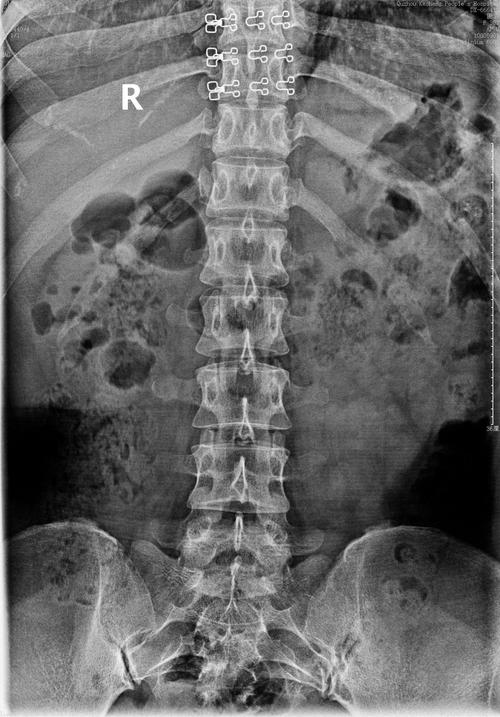

小朱腰椎的正位dr片